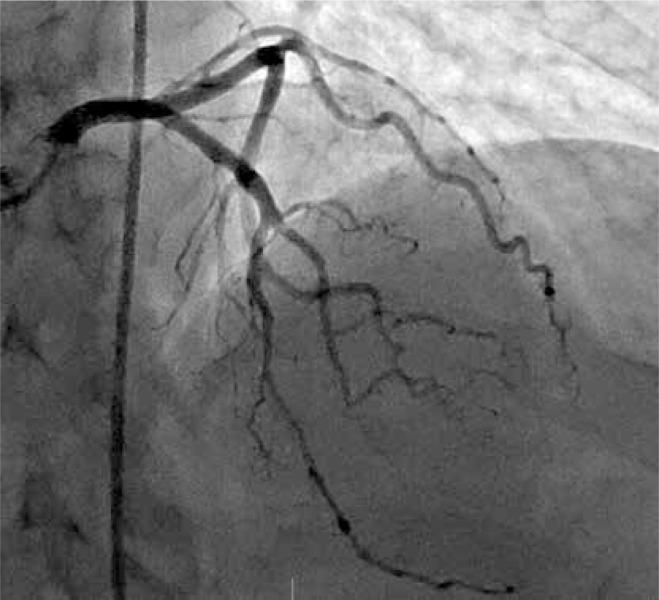

Should all coronary artery perforations be treated immediately?